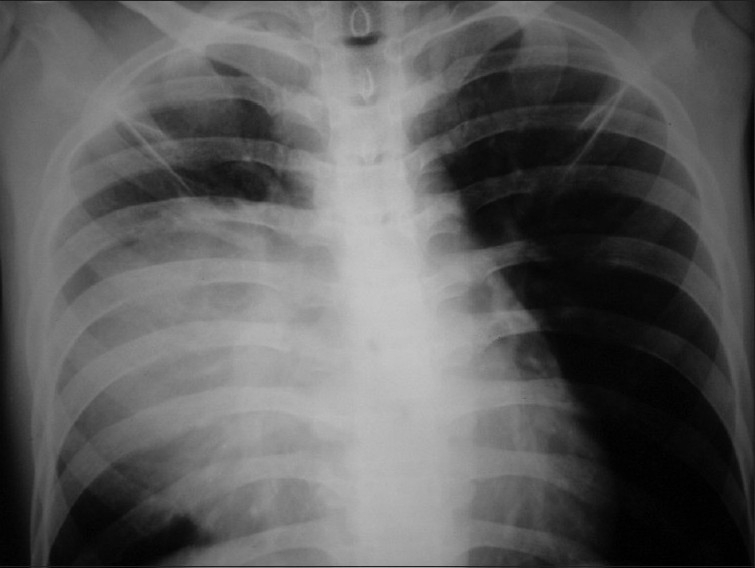

He presented in June 2007 with dull-aching retrosternal and right-sided chest pain with exertional dyspnea and dysphagia for solids. On examination, there was impaired note to percussion over the right mammary and infra-axillary regions with diminished breath sounds. A 3 ×3 cm mass was palpable over the epigastric region. Both testes were normal. Chest X-ray showed superior mediastinal widening with homogenous opacity in the right mid and lower zone [Figure 6]. CECT chest showed an anterior mediastinal mass extending into middle mediastinum with subpleural metastases to posterior segment of right lower lobe [Figure 7].

| Figure 6 Chest X ray PA view (2007) shows superior mediastinal widening with homogenous opacity in right mid and lower zone

The diagnosis of recurrent seminoma of thymus with metastases to right lung, para- and peri-aortic lymph nodes was made. The patient was started on BEP (bleomycin, etoposide, cisplatin). After four courses of chemo, complete disappearance of the mediastinal mass and lung metastatic lesions and reduction of abdominal lymph nodes to sub-centimeter size were noted [Figures [Figures99–11].

| Figure 9 Chest X ray PA view (2008 - post chemo) - disappearance of mass